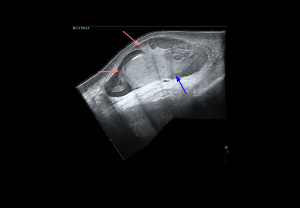

Grey-scale:

- Early (<6 h): normal echogenicity

- Acute (<6 h): testis enlargement, thickened scrotal coverings, reactive hydrocele, altered epididymal echogenicity or position.

- Late: reduced size, heterogeneous echotexture; hypoechoic areas

Doppler findings:

- Degree of torsion:

- Complete (≥360°): Usually absent intratesticular flow.

- Partial (<360°): Residual intratesticular flow may be detectable.

- Spectral Doppler: Increased resistive index (RI) and possible diastolic flow reversal, whirlpool sign of spermatic cord

- Late (>24 h): Periscrotal hyperaemia reflects inflammation.